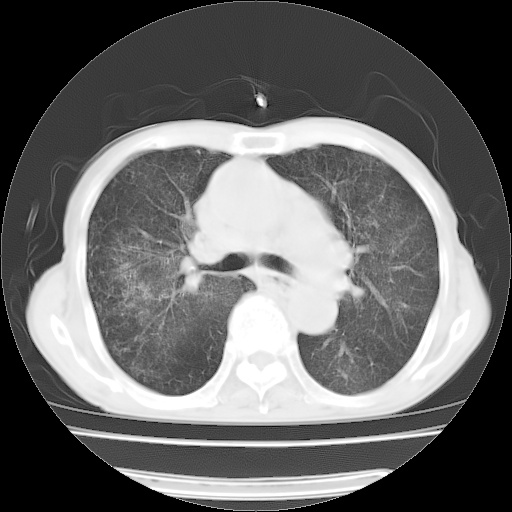

病人发热、气促就诊。原二周前已行ct扫描,当时诊断为双肺下叶、右肺中叶支气管扩张并感染,双肺上叶片状渗出性病变。今天复查胸部ct,双肺下叶支气管扩张并感染病灶较前明显吸收,但双肺上叶渗出性病变较范围较前明显增大。

双肺多发大片状、斑片状高密度渗出影,部分实变,考虑病毒性肺炎。